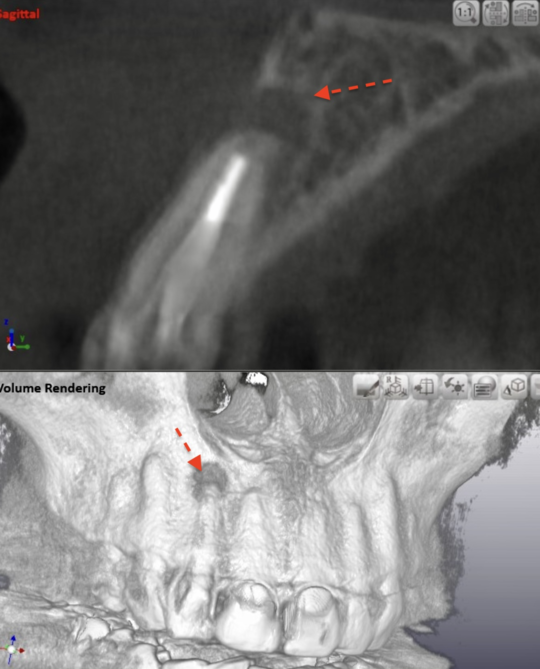

自費根管治療症例4 治療前(外科的歯内療法)

治療はしてありますが、根の先が黒ずんで見えます

唇側の顎骨が溶けて穴が空いています

精密根管治療(自費根管治療)治療開始

精密根管治療(自費根管治療)、治療回数2回、治療期間約2週間、治療費6万8千円+4,500円X1回

歯肉への切開が必要です、ウミの袋も取り出します